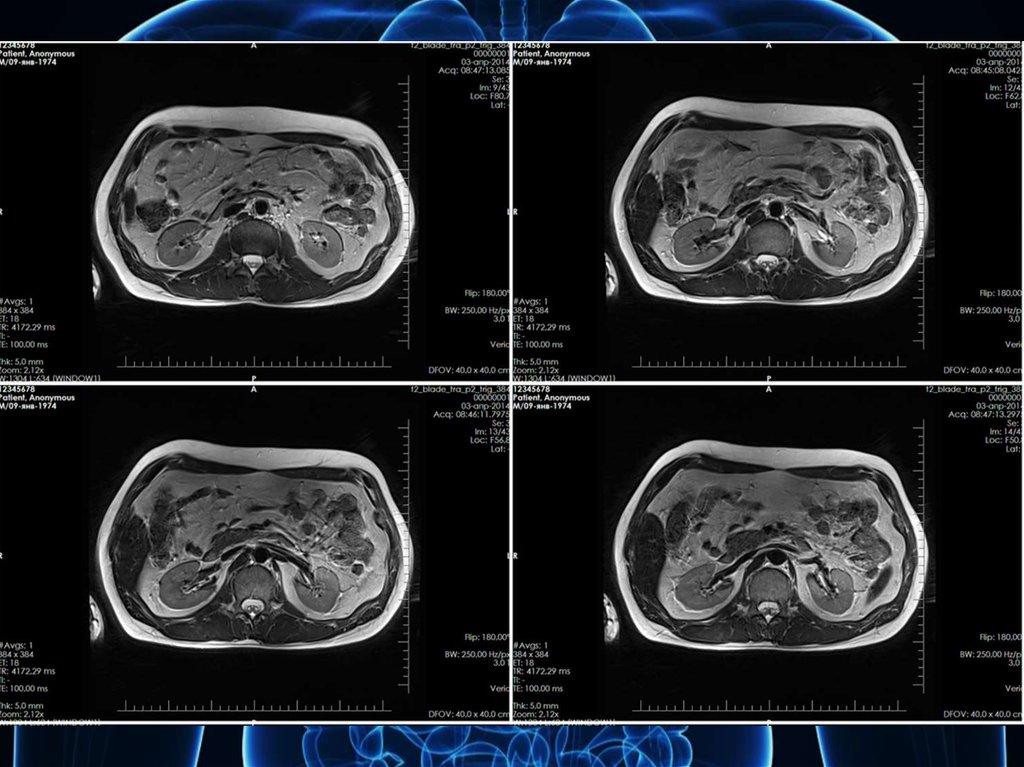

биопсия почек